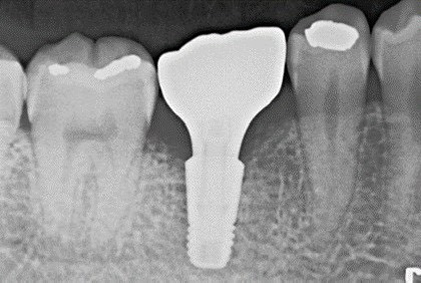

當牙齒因外傷或蛀牙缺失時,透過植入鈦金屬牙根,再安裝假牙,恢復原有牙齒的功能與美觀。

Before術前

After術後